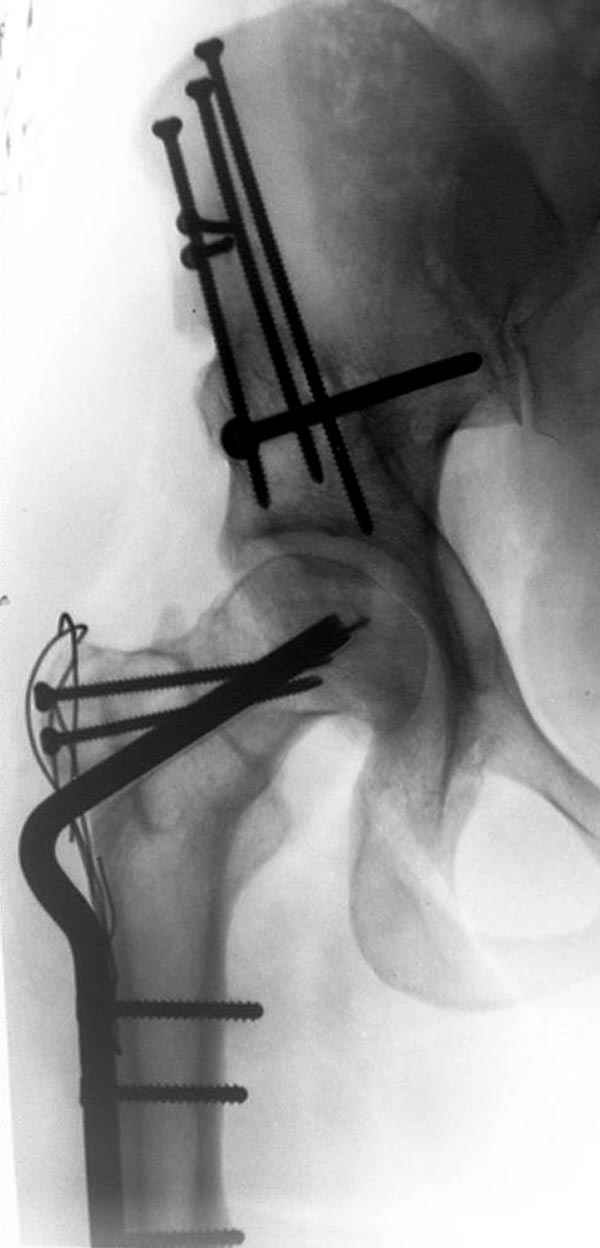

Depending upon surgeon preference, as well as availability of adequate operating room equipment and staff, this reconstruction can be done in two stages: periacetabular osteotomy with correction of acetabular retroversion would be the first stage. The second stage would involve a proximal femoral valgus osteotomy with neck lengthening.

In this second stage, a 120 degree blade plate can be used for correction proximal femur varus deformity. These procedures are both technically difficult, and require a great amount of pre-operative planning, both by the surgeons involved as well as the operating room staff.

Pic. 1-5 preop plan; 6-8 similar case